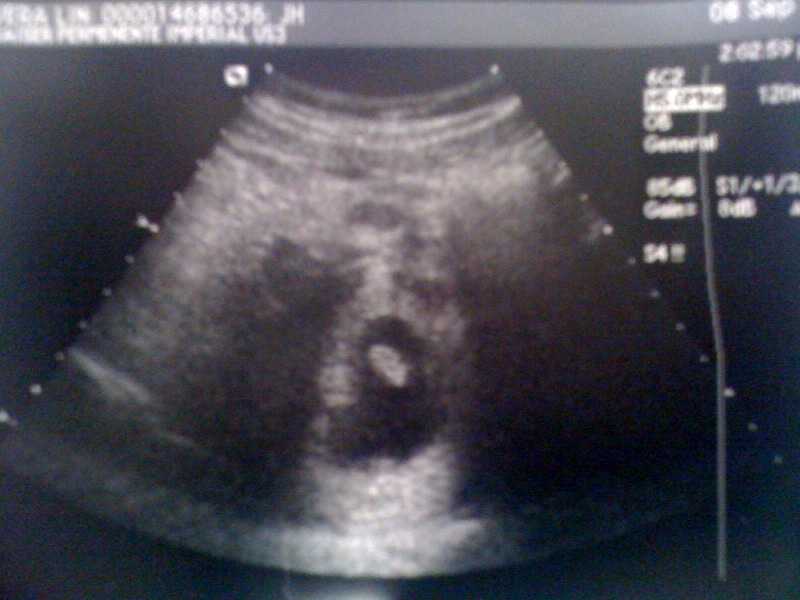

Someday this 1.59cm-er will find this entry stashed between all my peevish grumbles and fascination with trifles, then really question the meaning of life.